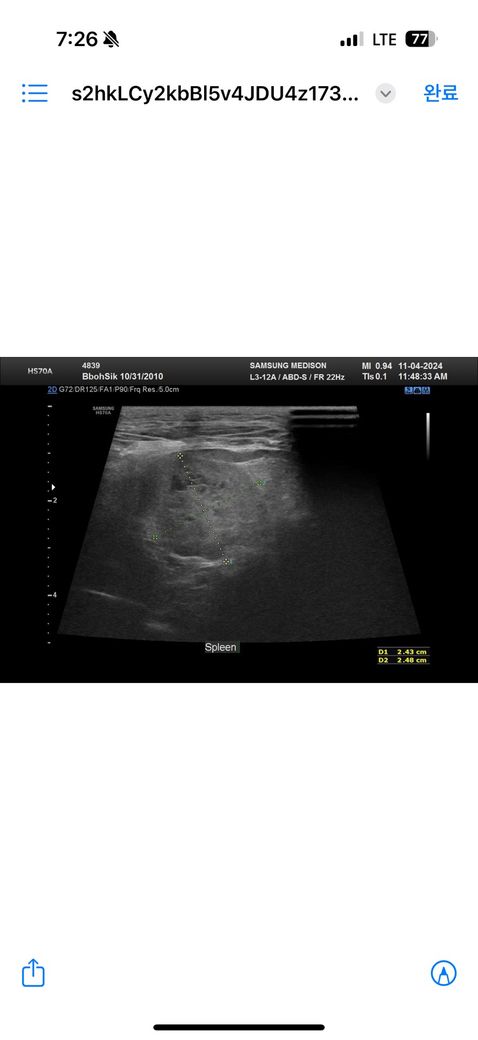

안녕하세요 최근 두군데에서 16살 노령견 복부초음파를 찍었습니다 그런데 두군데에서 서로 다른결과를 말씀하셔서요 한군데는 비장종괴 2.5cm 라고 하시고 한군데에서는 안커지는거보니 비장종괴가 아니라 부신종양이라고 말씀하시던데 뭐가 맞는지 모르겠어서요ㅠ 전에 초음파 찍은게 잇엇던거 같은데 사진 둘중에 뭔지는 잘 모르겟지만 혹시나 아시면 알려주실수있으실까요ㅜㅜ

종괴가 너무 크면 기원 평가에 제한이 있을 수 있으나 2.5cm 의 크기라면 구분하지 못하는 수준은 아닙니다. 이럴때는 영상전공의가 있는 동물병원에 가셔서 초음파 검사를 받고 소견 참조를 하는게 방법입니다. 모든 수의사가 초음파를 다 잘 보는것은 아니기 때문입니다.